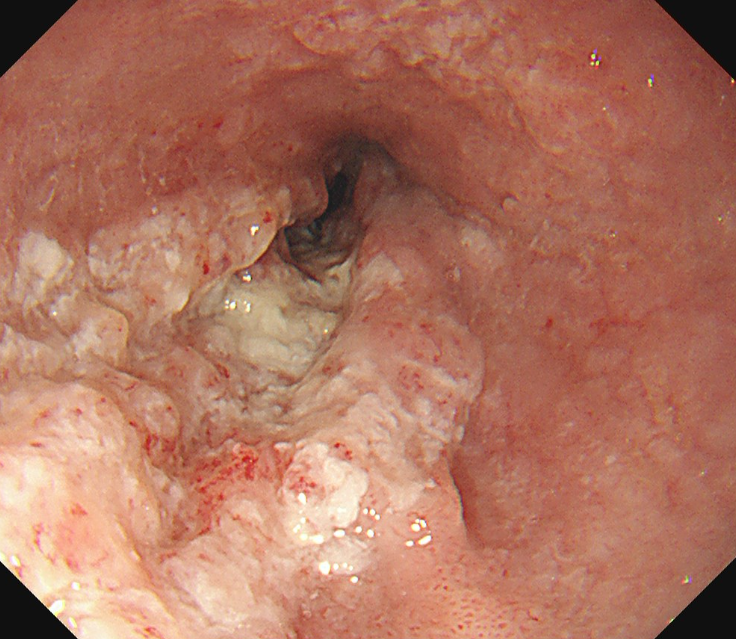

食道がんの検査は、がんかどうかを確定するための検査と確定された後に行う進行度を判断するための検査があります。まず確定するための検査としては、内視鏡(胃カメラ)で直接病変を観察する内視鏡検査が行われます。内視鏡で異常がみられる場合は組織を採取し、顕微鏡で観察する生検を行い診断が確定されます。

内視鏡(胃カメラ)画像